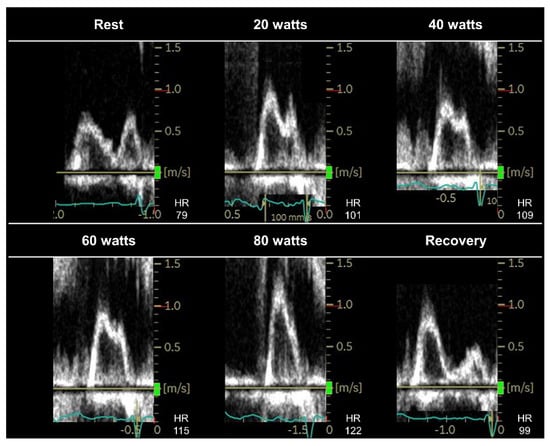

3.3. Stress Protocols, Image Acquisition, and Targeted Parameters

3.4. Interpretation of Test Results and Diagnosis of HFpEF